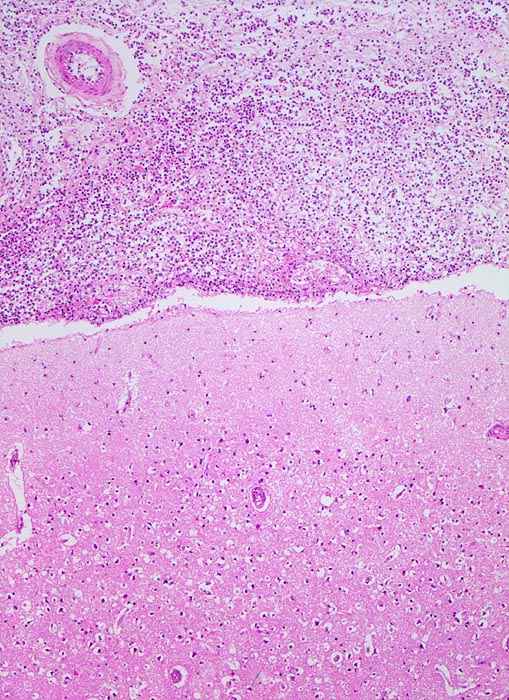

Eitrige Meningitis

Meningen

Zytologisch finden sich mehr als 90% neutrophile Granulozyten, ausserdem Fibrin, Makrophagen, degenerierende Zellen, Zelldetritus und manchmal Mikroorganismen. Nach Beginn der Antibiotikatherapie kommt es zu einem raschen Abfall der Zellzahl. Die neutrophilen Granulozyten degenerieren und aktivierte Monozyten beherrschen das Zellbild. Plasmozytoide Lymphozyten und Plasmazellen können dazukommen. In der Reparationsphase verschwinden die Granulozyten, die Anzahl Plasmazellen verringert sich, die Makrophagen sind degeneriert und haben vakuolisiertes Zytoplasma.